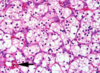

What are the KEY features on this H and E taken from a kidney tumor? Tumor Type?

•uniform round cells with abundant, intensely eosinophilic and granular cytoplasm = MITOCHONDRIA

***NOTABLY no PLEOMORPHISM***

•uniform small, round and central nuclei, Evenly dispersed chromatin

What is shown here?

• key features?

Oncocytoma

Key Features:

- Oncocytic = pink and grainy with sheets of pink and grainy PINK cells

- UNIFORM, not much pleomorphism

- smooth cell borders